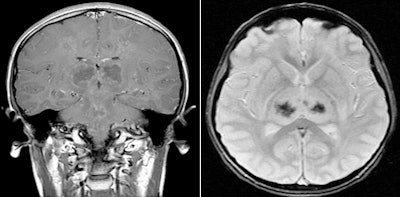

Abnormal rim enhancement of the bilateral thalami and magnetic susceptibility artifact in the bilateral thalami on T2-weighted images were also present. However, no abnormal meningeal enhancement was identified.

| Contrast-enhanced coronal T1-weighted image, left, demonstrates abnormal enhancement in the centrum semiovale and brainstem with ring-enhancing lesions in the thalami bilaterally. Axial T2-weighted gradient recalled echo image, right, demonstrates magnetic susceptibility bilaterally in the thalami. |